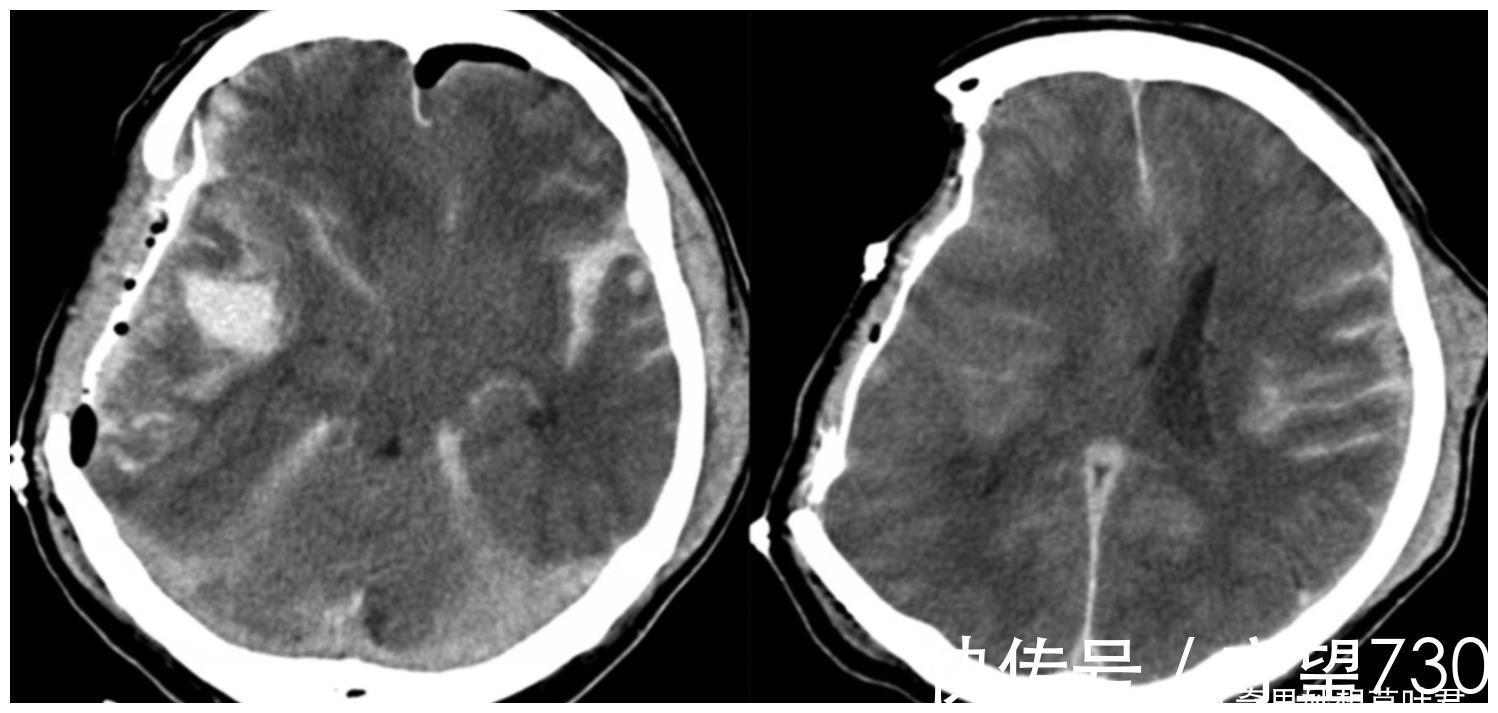

此时,医生决定进行一次脑部扫描,看看该男子的大脑是否有异常。当扫描结果出来时,医生惊呆了,因为这个 44 岁的法国男人没有大脑。这位医生在医学界多年从未见过这样的脑部扫描。这个人脑子应该是空的。

但出乎意料的是,医生仔细观察,这个男人的大脑和正常人完全不同,他的脑容量只有正常人的10%,而另一个零件完全消失。

因为这个病例确实少见,医院立即叫来了脑科专家会诊。经过进一步研究,发现该男子的头骨里充满了液体,外面只有一层。大脑组织的薄皮层,大脑内部几乎完全被液体占据。后来,医生得知这名法国男子在婴儿时期就患有“脑积水”。当时,医院在他的大脑中植入了治疗支架,定期排出多余的脑积水。

但在他14岁那年就取出了支架,因为医院觉得男孩的病情稳定,可以取出支架。然而,这并不重要。 30多年来,这个男人的大脑中的脑积水一直在增加,然后开始一点一点地侵蚀着他的大脑。现在被发现时,他的部分大脑已经被侵蚀了90%。 .